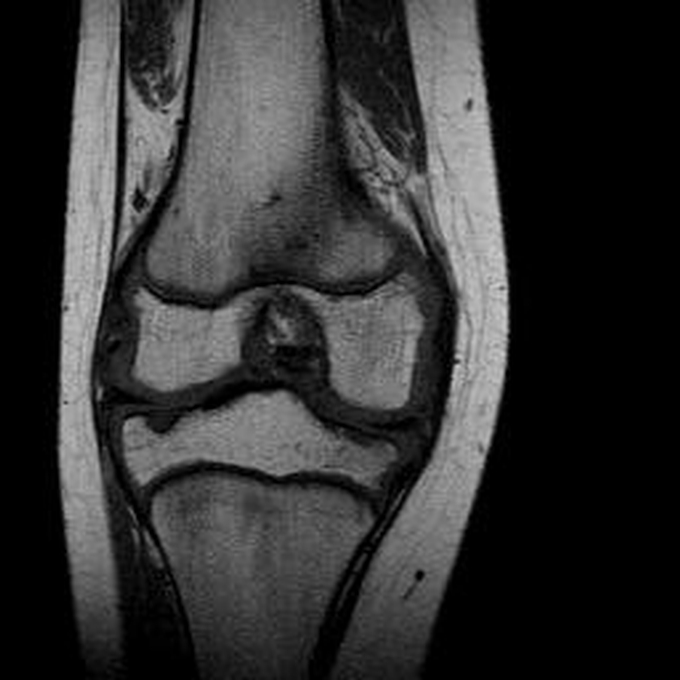

Haemophiliearthropathie bei Haemophilie A.

ARC123 Haemophiliearthropathie bei Haemophilie A.